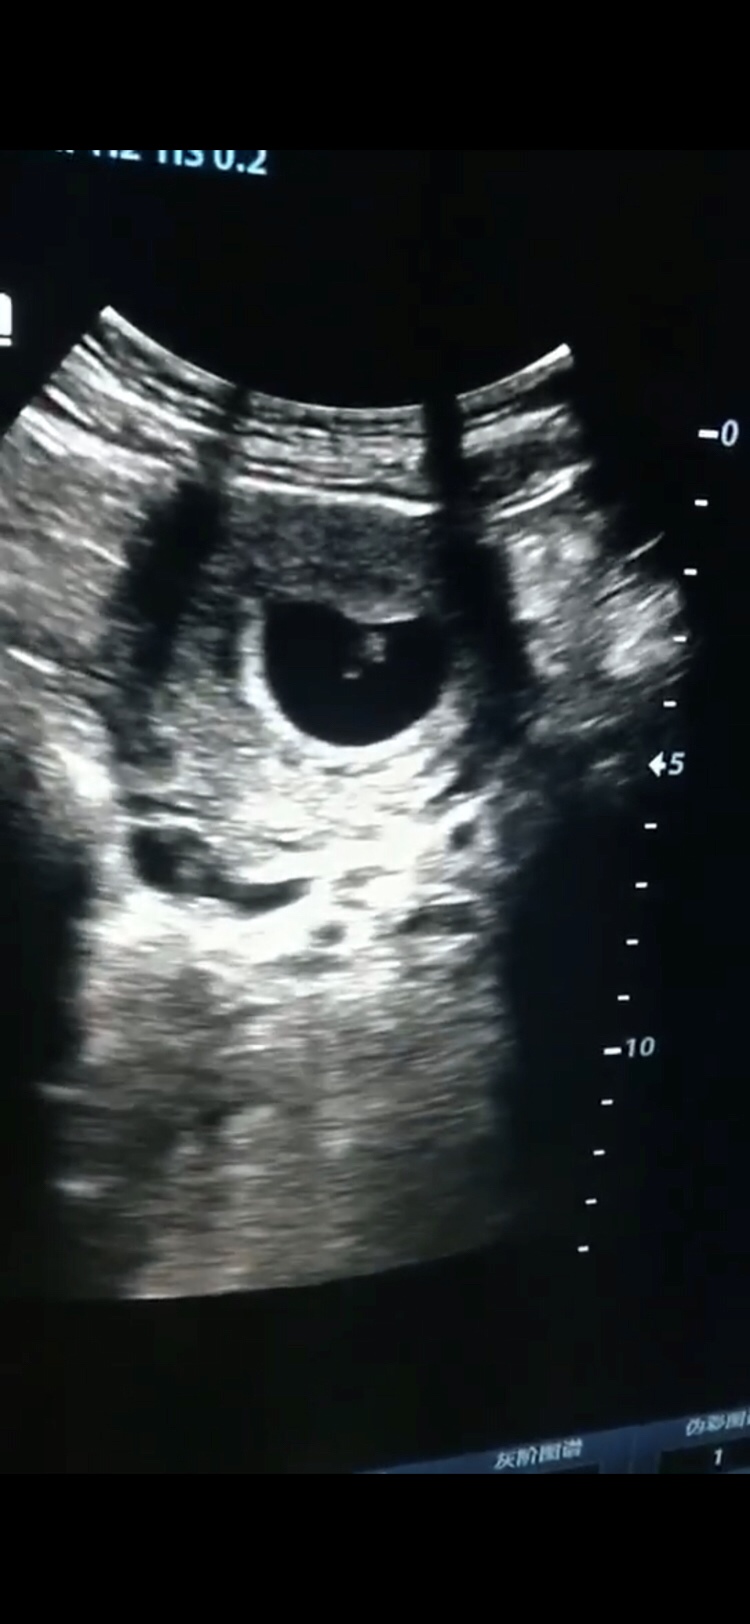

备孕中

备孕 夫妻生活

备孕 好孕指南